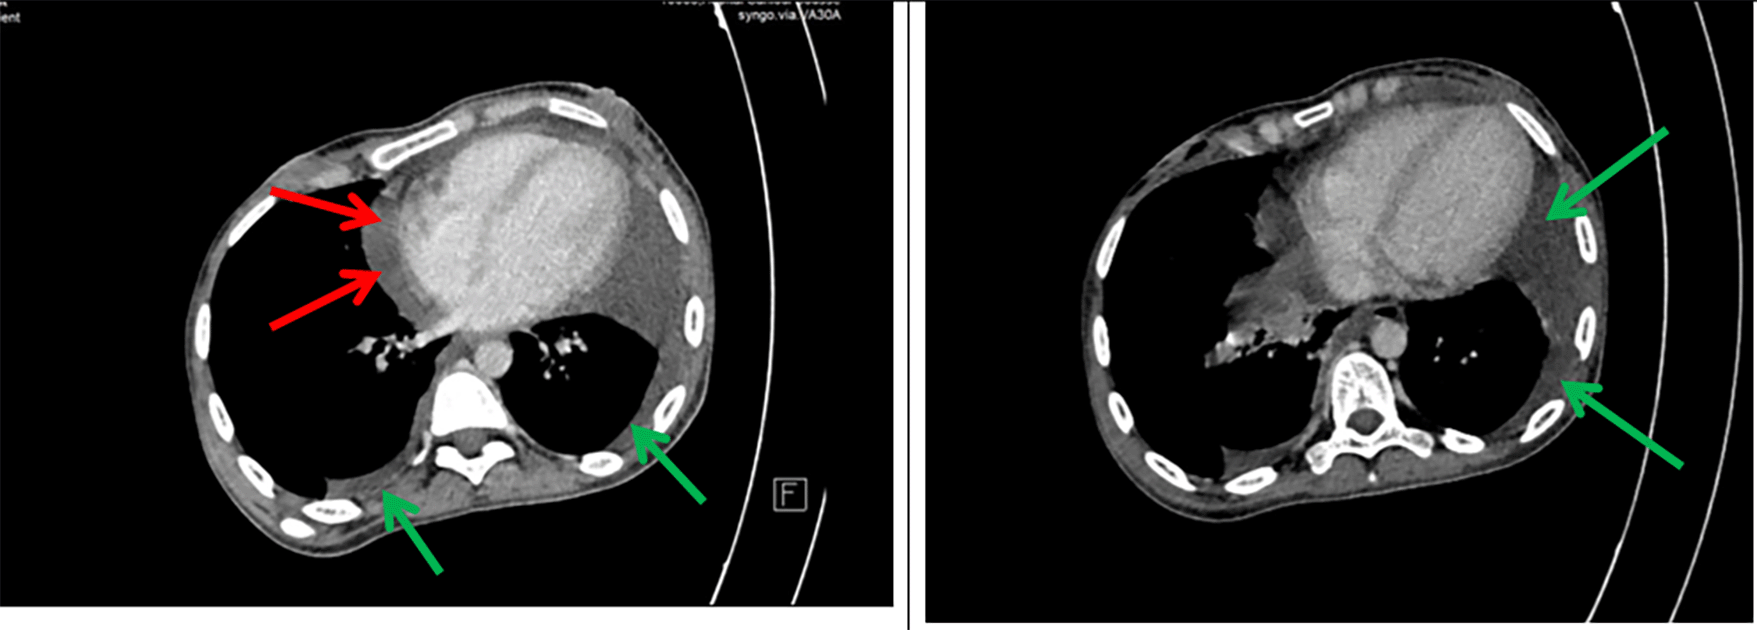

A 26-year-old- woman was referred to our hospital with abdominal pain for five days, fatigue, and fever (39°C). Her medical history included Crohn’s disease in 2018 with inflammation located in the terminal ileum and was taking azathioprine. The patient declared no exposure history to active tuberculosis in the past. Her heart rate was 121 beats per minute, blood pressure 110/77 mmHg, respiratory rate 25 breaths per minute, and temperature 39 °C. The patient had splenomegaly without hepatomegaly or adenopathy. Shifting dullness and a positive fluid wave test were found. No other signs were reported on physical examination. A chest X-ray was performed, showing bilateral pleural effusion compatible with tuberculosis. An abdominal CT scan was conducted, revealing the presence of both pleural effusion and a significant volume of ascites. High axial sections through the thoracic base showed bilateral pleural and pericardial effusion ( Figure 1).

Axial sections taken at portal time after injection of contrast agent showed abundant intra-peritoneal effusion ( Figure 2).